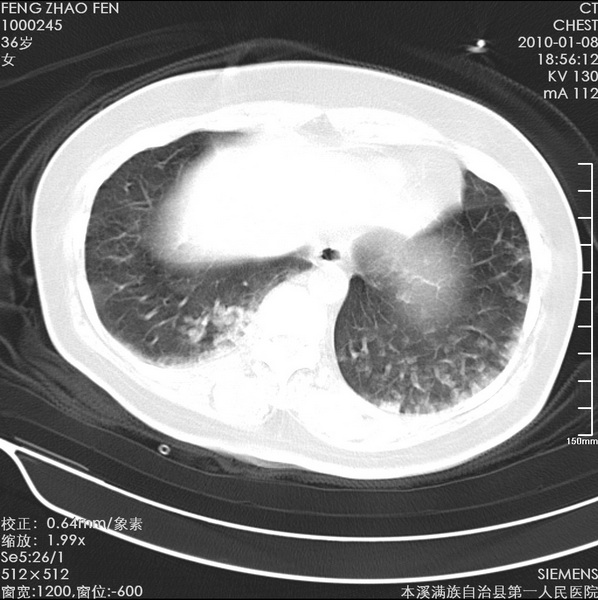

标题: CT24051:双肺多发斑片状阴影 [打印本页]

标题: CT24051:双肺多发斑片状阴影

女、36、咳嗽、咯血,余不详。